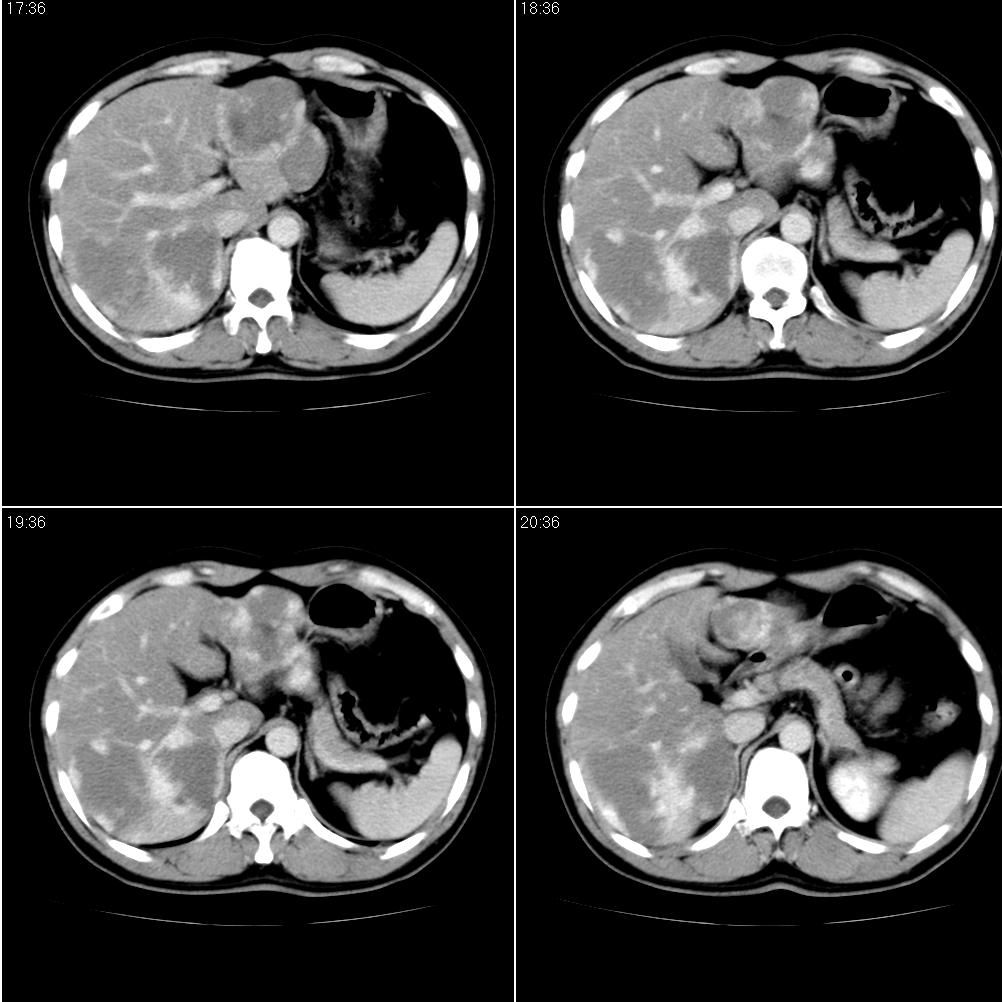

男,43岁。体检发现肝脏病变

结合增强扫描

我觉得肝左叶病变考虑fnh可能性最大。

增强后诊断很明确了,缓慢结节样强化:肝内多发血管瘤

从这个病例可以看出增强ct优势何其重要性和必要性。